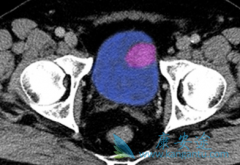

• 舒尼替尼(Suninat)治疗晚期肾癌间歇给药不影响生存期

舒尼替尼(Suninat)治疗晚期肾癌间歇给药不影响生存期

舒尼替尼 (Suninat)已被纳入转移性肾细胞癌(mRCC)一线治疗方案。但是服用舒尼替尼会出现手足综合征、腹痛、腹泻、心肌缺血等不良反应。如何平衡患者的临床获益和治疗带来的慢性毒性是应用舒尼替尼治疗mRCC的最大挑战。一项前瞻的Ⅱ期临床研究,评估 ...